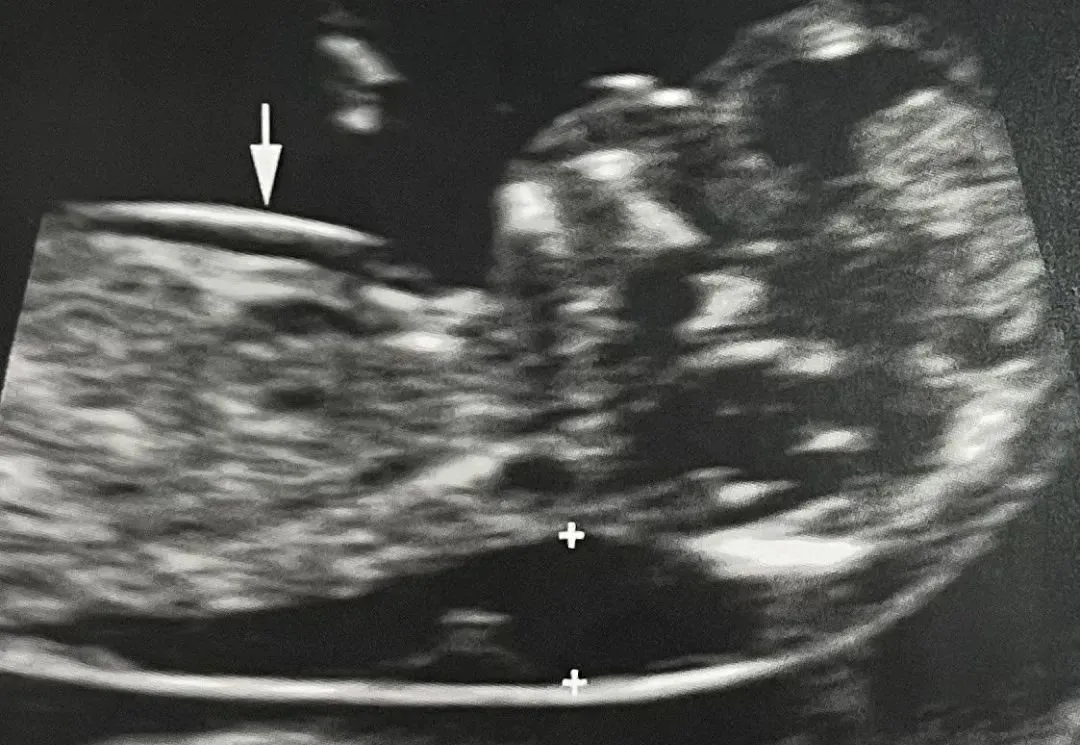

孕12周胎儿纵切面显示胎儿淋巴水囊瘤,向前(箭头)及向后(小箭头)延伸至整个胎体,形成光环样结构。脐膨出(细箭头)增加了该胎儿非整倍体的可能性。